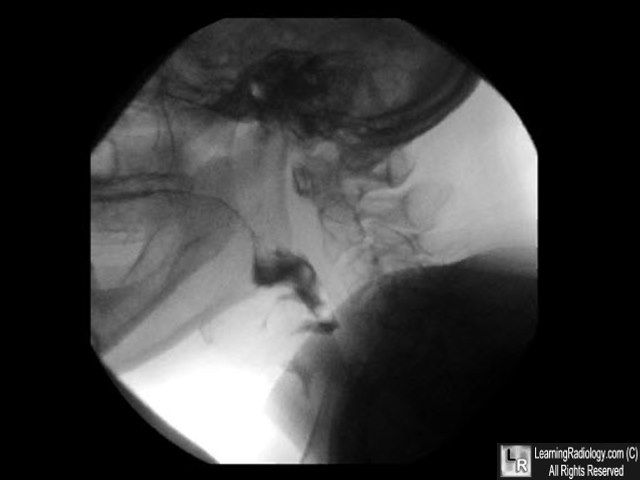

- 56 year-old with coughing after eating

Video Swallowing Study

Additional Images - One stop-action frame of study

One stop-action frame of study

4. Aspiration

- Aspiration represents material that passes through the true vocal cords into the trachea